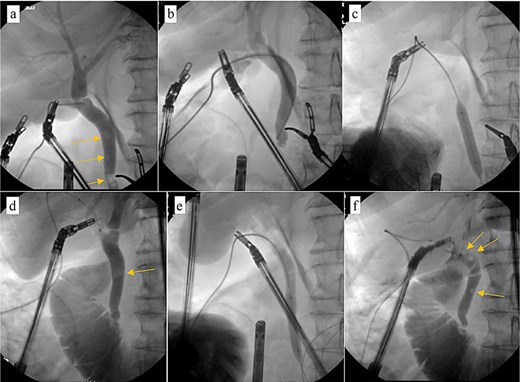

Patient was brought to the OR, induced, and the peritoneum was accessed via optical view trocar. After the critical view of safety was obtained, the cystic duct was partially transected and a 6-French ureteral catheter was threaded through the duct and into the CBD. Initial cholangiogram showed complete obstruction of the distal CBD. A 0.035 guidewire was advanced through the ureteral catheter. The ureteral catheter was then exchanged for a 9 × 40 mm long vascular balloon catheter. The balloon was then centered at the ampulla of vater and inflated to its nominal pressure for 5 min. A small indentation was noticed at the level of the ampulla once the balloon was fully insufflated, as expected. The completion cholangiogram showed prompt evacuation of contrast into the duodenum. However, numerous “floating” filling defects continued to be present (Fig. 4). The decision was thus made to leave a T-tube in place via a 1-cm longitudinal choledochotomy. The incision was reapproximated around the t-tube with interrupted 4–0 PDS. The vascular balloon catheter was removed, the cystic duct was completely transected, and the gallbladder was dissected off the liver bed.

Intraoperative cholangiogram. (a) Initial cholangiogram via 6-fr ureteral stent showing multiple filling defects (arrows). (b) Guidewire passed through the ureteral stent and down to the level of the ampulla of vater, demonstrating complete CBD obstruction. (c) 7 × 40 mm vascular catheter balloon advanced over the guidewire and through the ampulla of vater. Dilated to nominal pressure. (d) Contrast now able to leave the CBD and into the duodenum. Residual “floating” filling defects still seen (arrows). (e) Vascular catheter exchanged for a 9 × 40 mm balloon and dilated to nominal pressure. (f) Completion cholangiogram shows brisk outflow of contrast with residual filling defects (arrows).